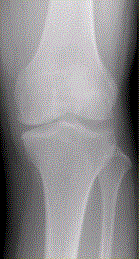

问题 患者女,54岁,右膝关节痛。实验室检查:类风湿因子阳性,除外膝关节类风湿性关节炎。X线检查结果如下图。 X线平片表现不包括

选项 A.关节边缘骨赘形成 B.关节边缘骨侵蚀 C.关节间隙不均匀变窄 D.关节囊肿胀 E.股骨内侧髁关节面下局限性硬化

答案 B